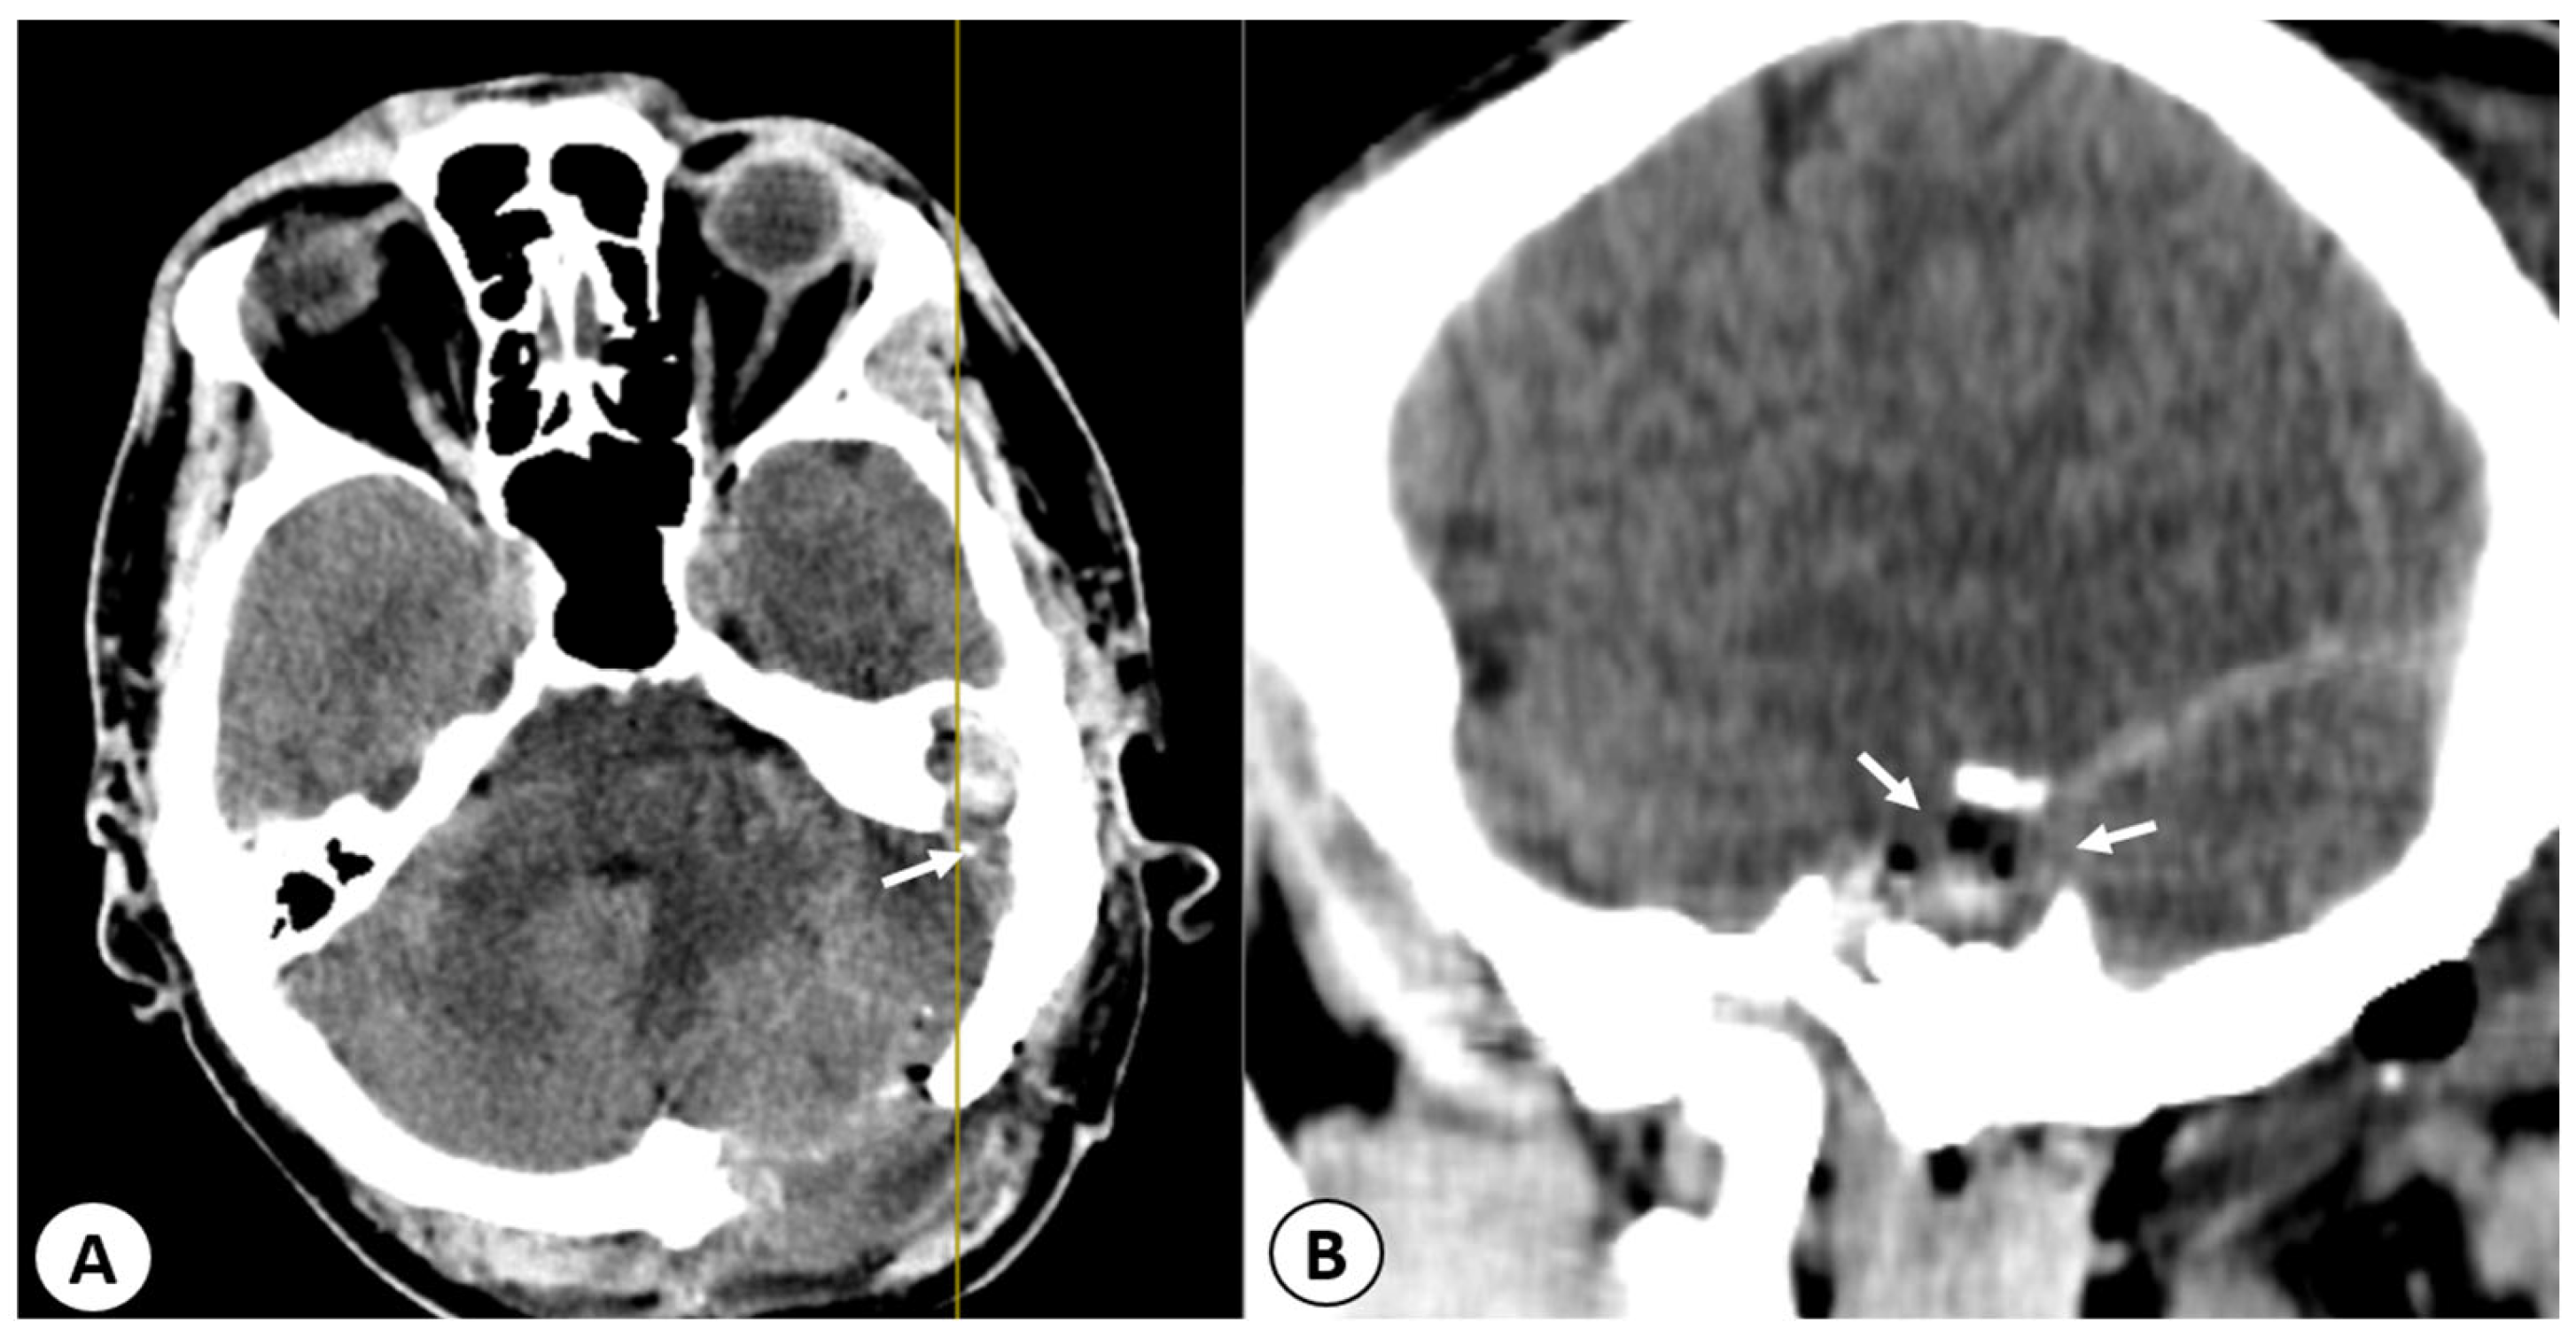

2.2.2. Imaging Studies

3.5. Imaging Studies